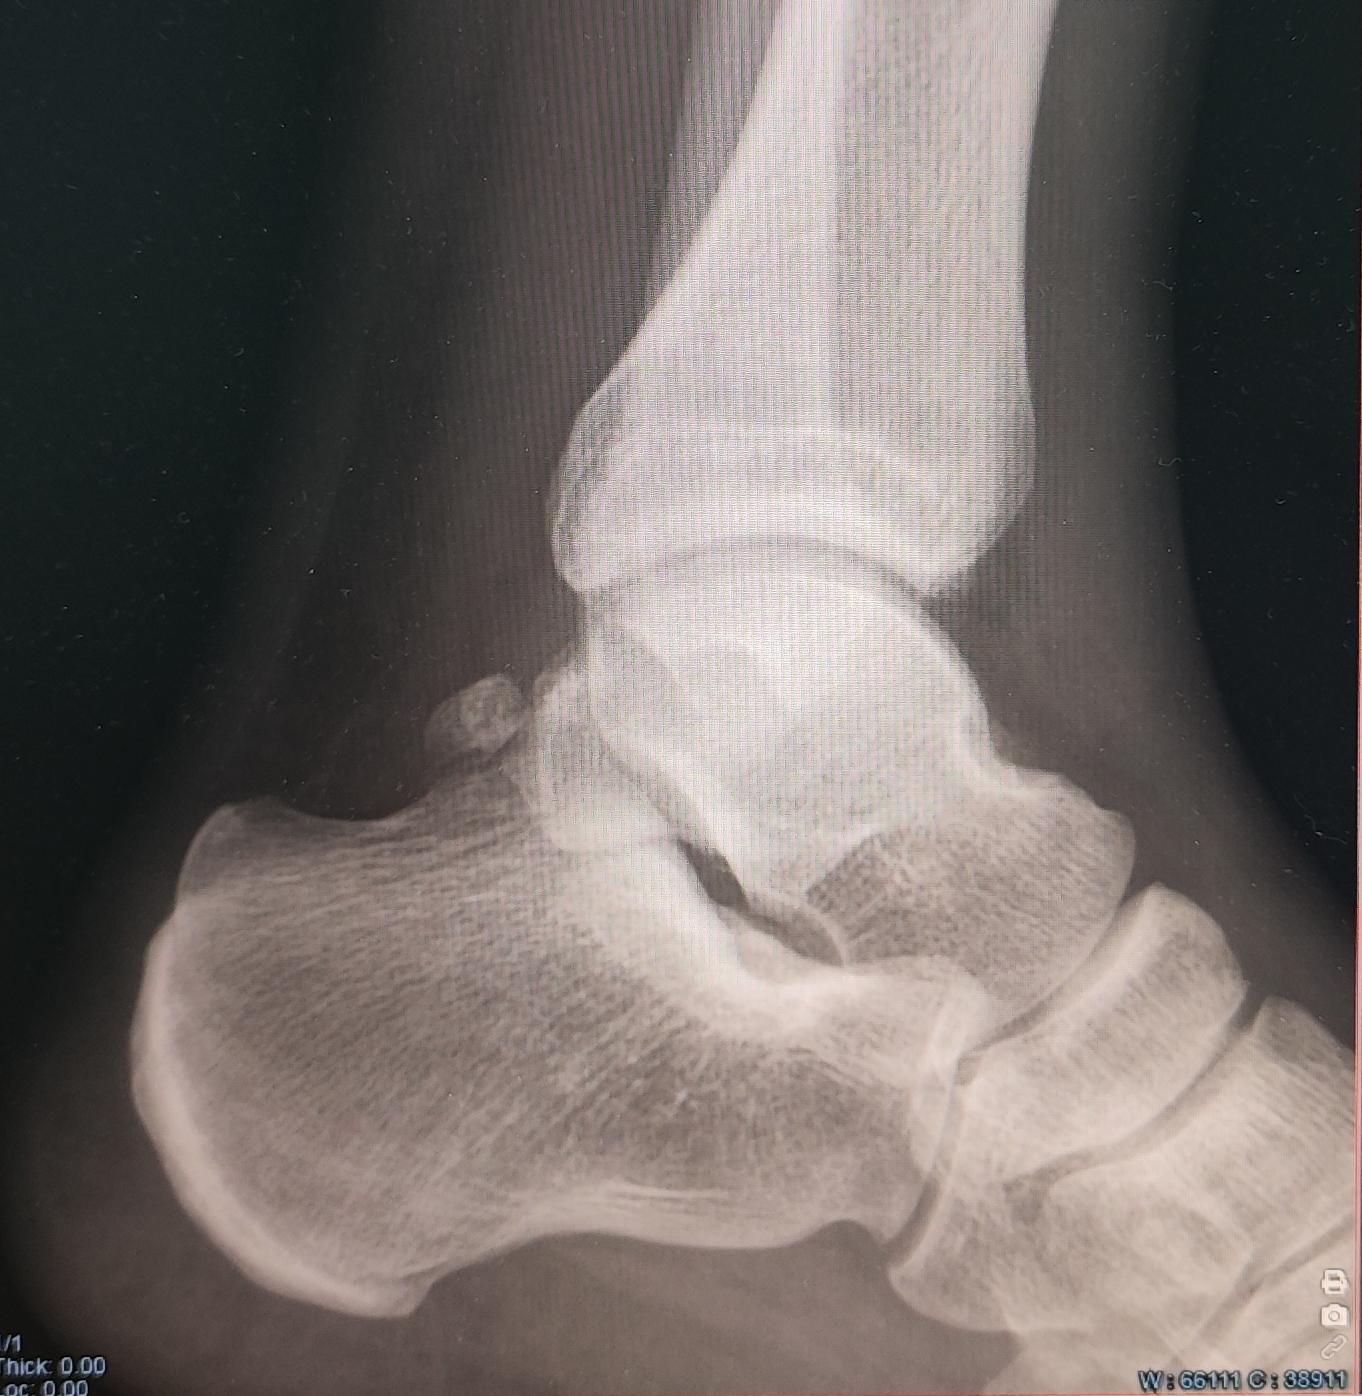

Описание: на Р-граммах левого гс/с в 2х проекциях суставная щель не сужена, субхондральный склероз, краевые остеофиты-не выявлены. По заднему контуру таранной кости определяется наличие дополнительной кости-os trigonum. Заключение:Os trigonum(аномалия развития левой стопы), наиболее вероятно вызывающая синдром компрессии таранной кости.